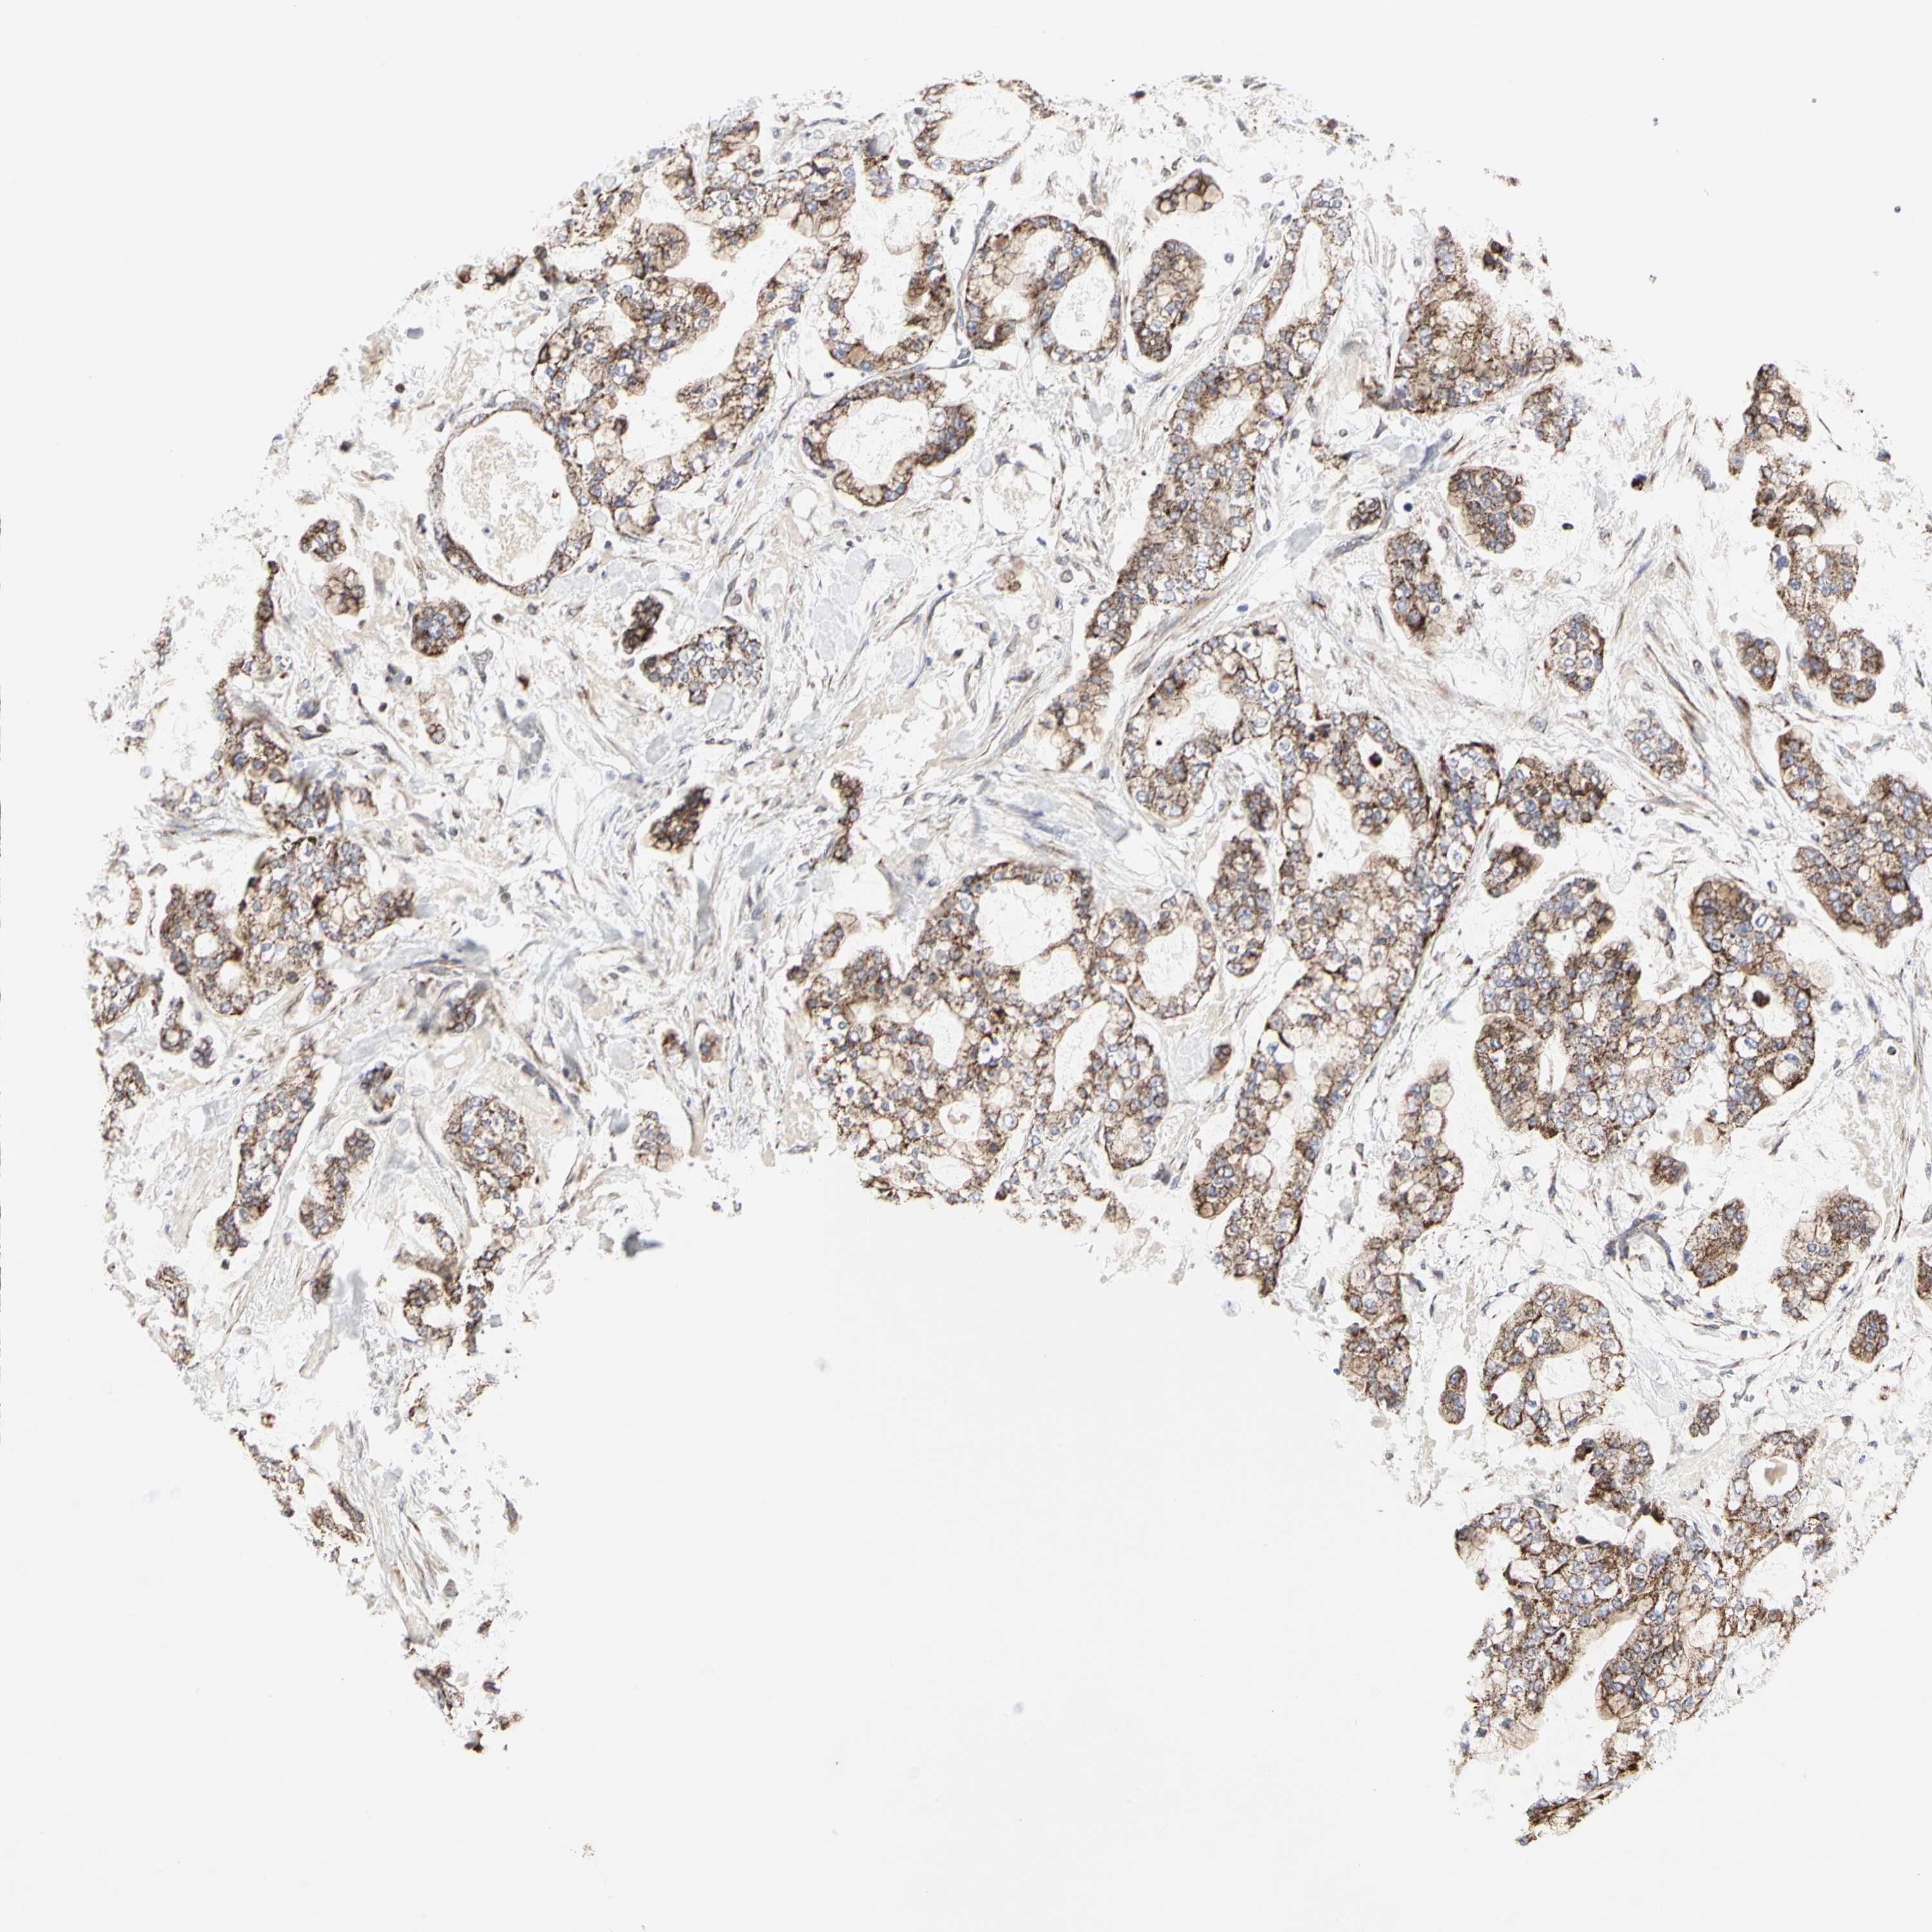

STOMACH CANCER - Protein expressioni

A mouse-over function shows sample information and annotation data. Click on an image to view it in a full screen mode. Samples can be filtered based on level of antibody staining by selecting one or several of the following categories: high, medium, low and not detected. The assay and annotation is described here.

Note that samples used for immunohistochemistry by the Human Protein Atlas do not correspond to samples in the TCGA dataset.

Antibody stainingi

Antibody staining in the annotated cell types in the current human tissue is reported as not detected, low, medium, or high, based on conventional immunohistochemistry profiling in selected tissues. This score is based on the combination of the staining intensity and fraction of stained cells.

Each image is clickable and will lead to virtual microscopy that enables deeper exploration of all samples and also displays staining intensity scores, fraction scores and subcellular localization as well as patient and tissue information for each sample.

Antibody HPA008164

Staining

High

Medium

Low

Not detected

Intensity

Strong

Moderate

Weak

Negative

Quantity

>75%

75%-25%

<25%

None

Location

Nuclear

Cytoplasmic/membranous

Cytoplasmic/membranous,nuclear

Adenocarcinoma, NOS